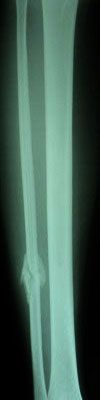

Fraktur tulang adalah cedera serius yang sering terjadi akibat berbagai kecelakaan atau aktivitas fisik yang berlebihan. Identifikasi fraktur tulang dengan cepat dan tepat sangat penting untuk menentukan perawatan yang sesuai. Salah satu pendekatan untuk mengidentifikasi fraktur tulang adalah melalui analisis citra radiografi. Dalam artikel ini, akan dijelaskan bagaimana pengolahan citra, khususnya dengan metode deteksi tepi Canny dan ekstraksi ciri menggunakan metode moment invariant, dapat digunakan untuk identifikasi fraktur tulang tibia dan fibula dengan bantuan algoritma Support Vector Machine (SVM).

Langkah pertama dalam identifikasi fraktur tulang adalah mendapatkan citra radiografi dari daerah yang terkena dampak. Citra radiografi ini biasanya diambil dengan menggunakan peralatan medis yang sesuai.